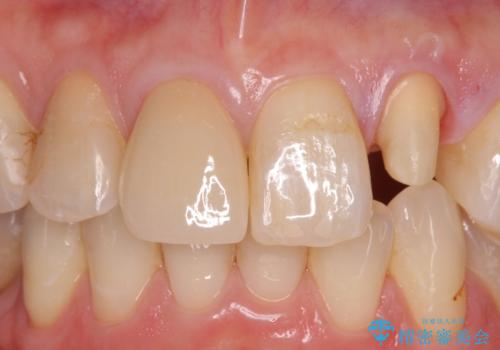

前歯を綺麗にしたい。 ジルコニアクラウンでの修復

- 継ぎ接ぎになった前歯を綺麗にしたいとのことで来院されました。

継ぎ目のないクラウンで修復処置していきます。

精度の良い被せ物を装着することで、違和感のない自然な見た目を獲得することができます。